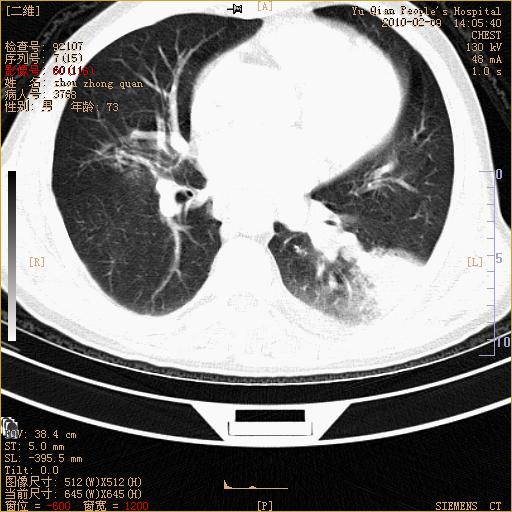

男性,73岁,咳嗽咳血数天,诊为肺ca伴左肺下叶后段阻塞性炎症、肺不张妥否?

右下肺有转移?

左下肺中央型肺癌伴结段形肺不张,左侧胸腔积液,纵隔内见部分增大淋巴结(反应性增生或转移)

左下基底干支气管明显变窄。

左肺下叶基底段支气管狭窄,左肺门增大,左肺下叶团片状病灶。中心型肺癌伴柱塞性炎症可能大,建议支气管镜检查。

左下肺中央型肺癌伴节段性肺不张,左侧胸腔积液,纵隔内见肿大淋巴结

左下基底段支气管变窄。建议进一步纤支镜检查。

1、左肺下叶后基地段肺癌伴阻塞性炎症,左下肺门淋巴结转移。2、左侧胸腔积液。